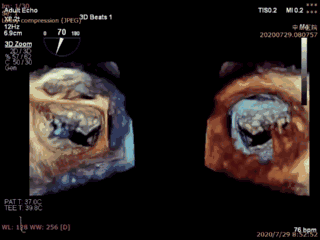

本例患者是一名70岁男性,术前超声心动图显示二尖瓣后叶冗长(前叶长度26mm,后叶长度20mm),瓣环前后径32mm,后叶p2关闭脱垂、连枷(脱垂宽度16mm,反流面积23.5cm2)。如此广泛的脱垂,使用国外同类产品完成经导管二尖瓣修复也是有极大挑战,经葛均波院士团队评估,多学科充分讨论后决定为该患者实施Valve Clamp二尖瓣夹合术。

首先在食道超声引导下,植入1枚IIIs型二尖瓣夹合器,释放后显示二尖瓣后叶仍有脱垂连枷,反流为轻中度,为改善患者远期疗效,遂再次植入1枚IIs型二尖瓣夹合器于A2P2的后瓣残余分流处,复查超声显示二尖瓣反流完全消失(0级),整个手术切口出血量几乎为零,手术取得圆满成功。